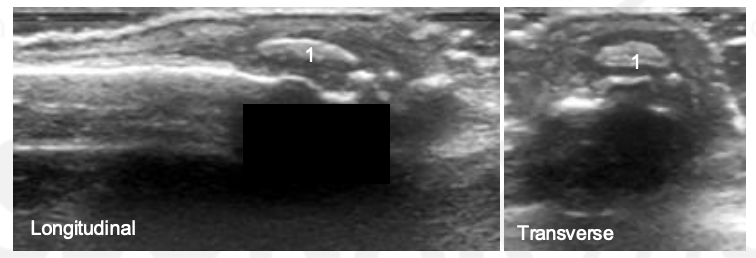

What is 1?

This is extensor calcification tendinopathy at the PIP.

What is 1 and 2?

CPPD at the MCP

What is 3?

This is the interface sign in a normal MCP